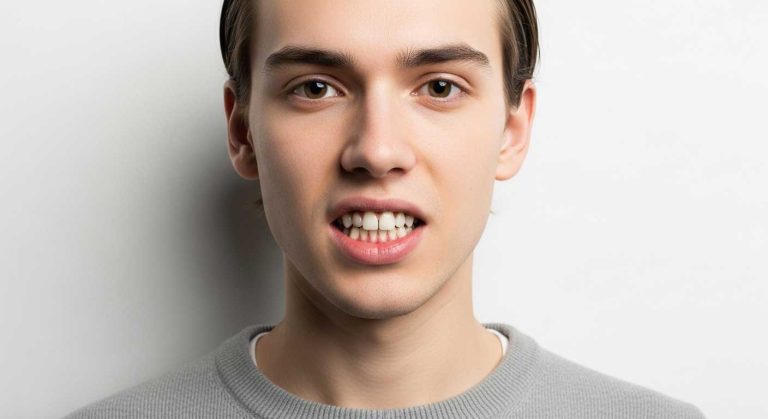

اورجت (Overjet) یا بیرون زدگی دندان های بالا

در حالت اورجت، دندان های پیشین فک بالا به طور قابل توجهی جلوتر از دندان های پیشین فک پایین قرار دارند. این وضعیت، که گاهی به آن “دندان های خرگوشی” نیز گفته می شود، می تواند زیبایی و عملکرد را تحت تأثیر قرار دهد و از نحوه درست قرار گرفتن دندانها فاصله دارد.